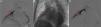

A contrast-enhanced computed tomography scan of the chest showed a pulmonary artery pseudoaneurysm with a maximum diameter of 45 mm at the right middle lobe, which was enhanced by contrast (Figure 1A and B). Pulmonary angiography confirmed the diagnosis (Figure 2A). After consultations with the respiratory medicine and interventional radiology departments, a percutaneous stent graft implantation was planned, in which a 6F multipurpose guiding catheter (Cordis) was placed and a PT2TM guide wire was positioned distal to the aneurysm. Under angiographic control a 3.5 mm×18 mm stent (BeGraft Peripheral Stent Graft System, Bentley Innomed) was placed in the pulmonary artery. This procedure was successful and there were no complications (Figures 2B and C).

Pulmonary angiogram confirming the presence and location of the pulmonary artery pseudoaneurysm (arrow), showing its extent: (A) anteroposterior view, with stent graft implantation (arrow) to treat the pseudoaneurysm; (B) anteroposterior view, showing an excellent result with unrestricted blood flow into the periphery when the bleeding had stopped (arrow); (C) anteroposterior view.